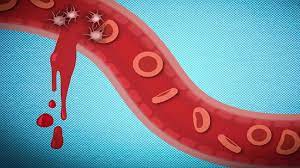

قیمت: 52٬000 تومان - دسته بندی فایل: پاورپوینتدانلود پاورپوینت خونریزی

دسته بندی : پاورپوینت , تعداد اسلاید : 30 اسلاید , خونریزی به از دست دادن خون یا خروج خون از دستگاه گردش خون گفته می شود